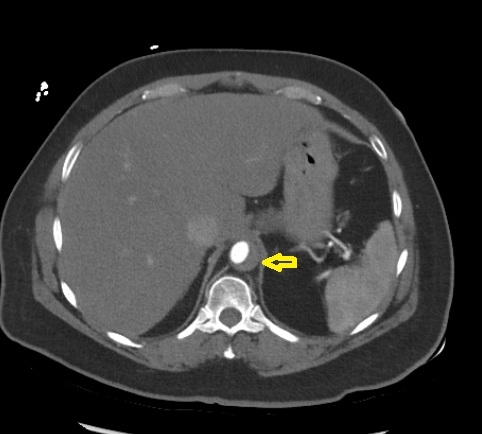

Given persistent suspicion for acute aortic syndrome, a dedicated CT angiogram of the aorta was performed, revealing an extensive intramural hematoma involving the aortic root, ascending aorta, arch, descending aorta, and abdominal aorta above the renal arteries.

An esmolol infusion was initiated, and cardiothoracic surgery was urgently consulted. Imaging was interpreted as most consistent with a penetrating aortic ulcer and sub-adventitial hematoma. The patient underwent emergent surgical replacement of the ascending aorta and hemiarch. Intraoperative transesophageal echocardiogram did not reveal aortic regurgitation or pericardial effusion.